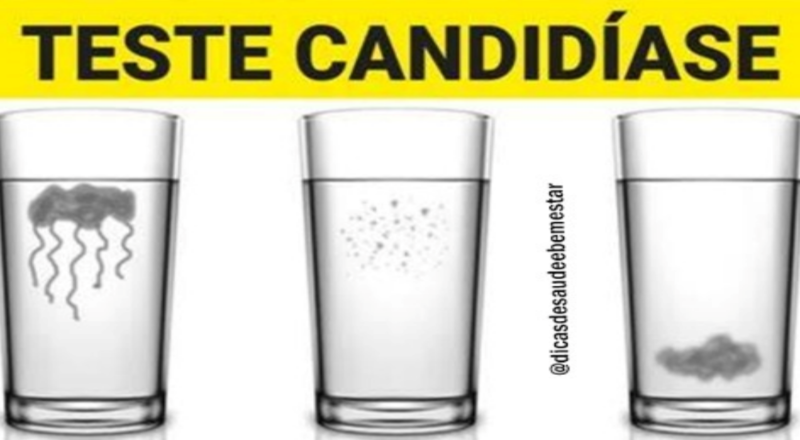

Continue lendoCandidíase: teste caseiro para verificar a presença da infecção

A candidíase é uma infecção fúngica comum causada pelo crescimento excessivo do fungo Candida albicans. Esta condição pode afetar várias partes do corpo, incluindo a […]